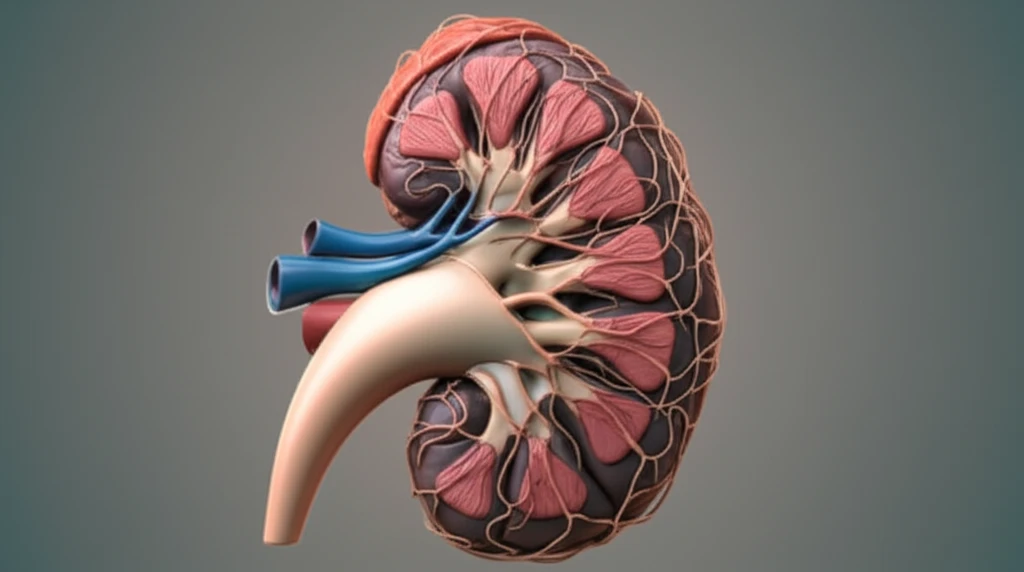

Kidney cancer is a formidable health challenge, and understanding its behavior is crucial for effective treatment. One of the critical aspects of managing kidney cancer involves determining if the cancer has spread to the lymph nodes, a process known as lymph node invasion (LNI). This information is vital for staging the cancer, planning treatment, and predicting outcomes.

Adding to the complexity, past research using cadaveric dissections and sentinel-node studies has highlighted significant variability in how the lymphatic system drains from the kidneys. These studies have shown that the lymphatic vessels can reach retroperitoneal nodes or even connect directly to supraclavicular and mediastinal nodes, bypassing typical drainage routes. This unpredictability raises questions about whether the location of the primary tumor within the kidney affects the likelihood of lymph node involvement.